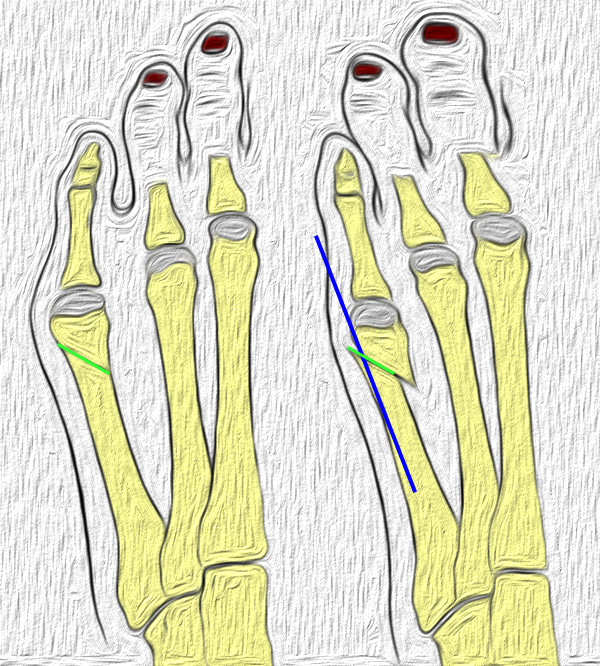

Abb. 6: Skizze der Chevron Osteotomie am Os metatarsale V.

Abb. 7 a, b: Typ II Deformität mit prä- (a) und postoperativem Röntgenbild (b) mit K-Draht Osteosynthese und gleichzeitiger Hallux valgus Korrektur.

Abb. 8 a, b, c: Typ III Deformität mit prä- (a) und postoperativem Röntgenbild (b, c) mit Schrauben-Osteosynthese.

Abb. 9 a, b: Typ III Deformität mit prä- (a) und postoperativem Röntgenbild (b).